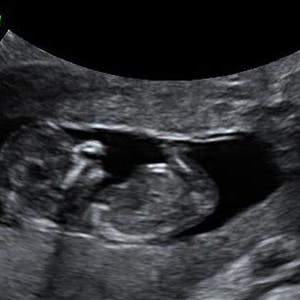

Gravid

Vi gør en dyd ud af at klæde dig godt på både før, under og efter din graviditet. Vi ved, at der kan komme mange spørgsmål til din graviditet, fødsel, amning, din babys udvikling og mange flere emner, derfor har vi samlet guides, tips & tricks samt læsernes egne fortællinger i dette gravid univers.